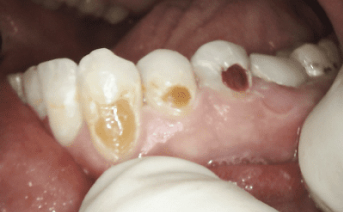

Our composite dental fillings in Atlanta, Georgia, not only fill in cavities, but can treat various cosmetic treatments by filling in teeth that have been damaged or demineralized. Schedule your treatment at Smiles of Atlanta with our dentist, to see if you need a composite dental filling from Dr. Ed Trizzino. Call 770-777-0808 today.